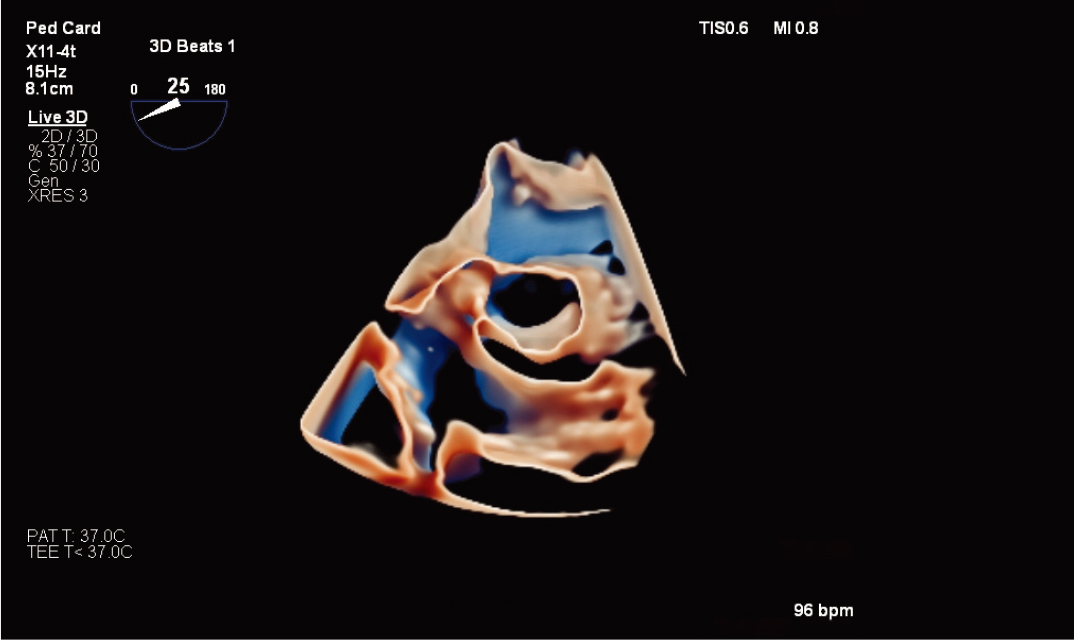

10适用于狭窄空间和复杂情况I使用全新 X11-4t 迷你 3D TEE 探头¹¹*,扩大 3D TEE 的应用范围。这款探头非常适合体型最小、体弱的患者,可扩大对儿科和成人患者的扫描范围。高效地执行手术,提高患者舒适度。X11-4t 探头与飞利浦创新产品组合集成,可与 VeriSight Pro 3D ICE** 在图像引导治疗中互补。

![]()

清晰、优质的 3D TEE 图像。

X11-4t 探头

X11-4t 探头进行儿科左心耳评估 |

X11-4t 探头和 TrueVue 进行瓣下膜检查 |

X11-4t 探头和 TrueVue Glass 进行三尖瓣 MPR 成像。 |

使用 VeriSight Pro 进行 xPlane 成像 |

X11-4t 探头的儿科 3D 彩色 |

主动脉瓣的 MPR 视图和 TrueVue 容积 |